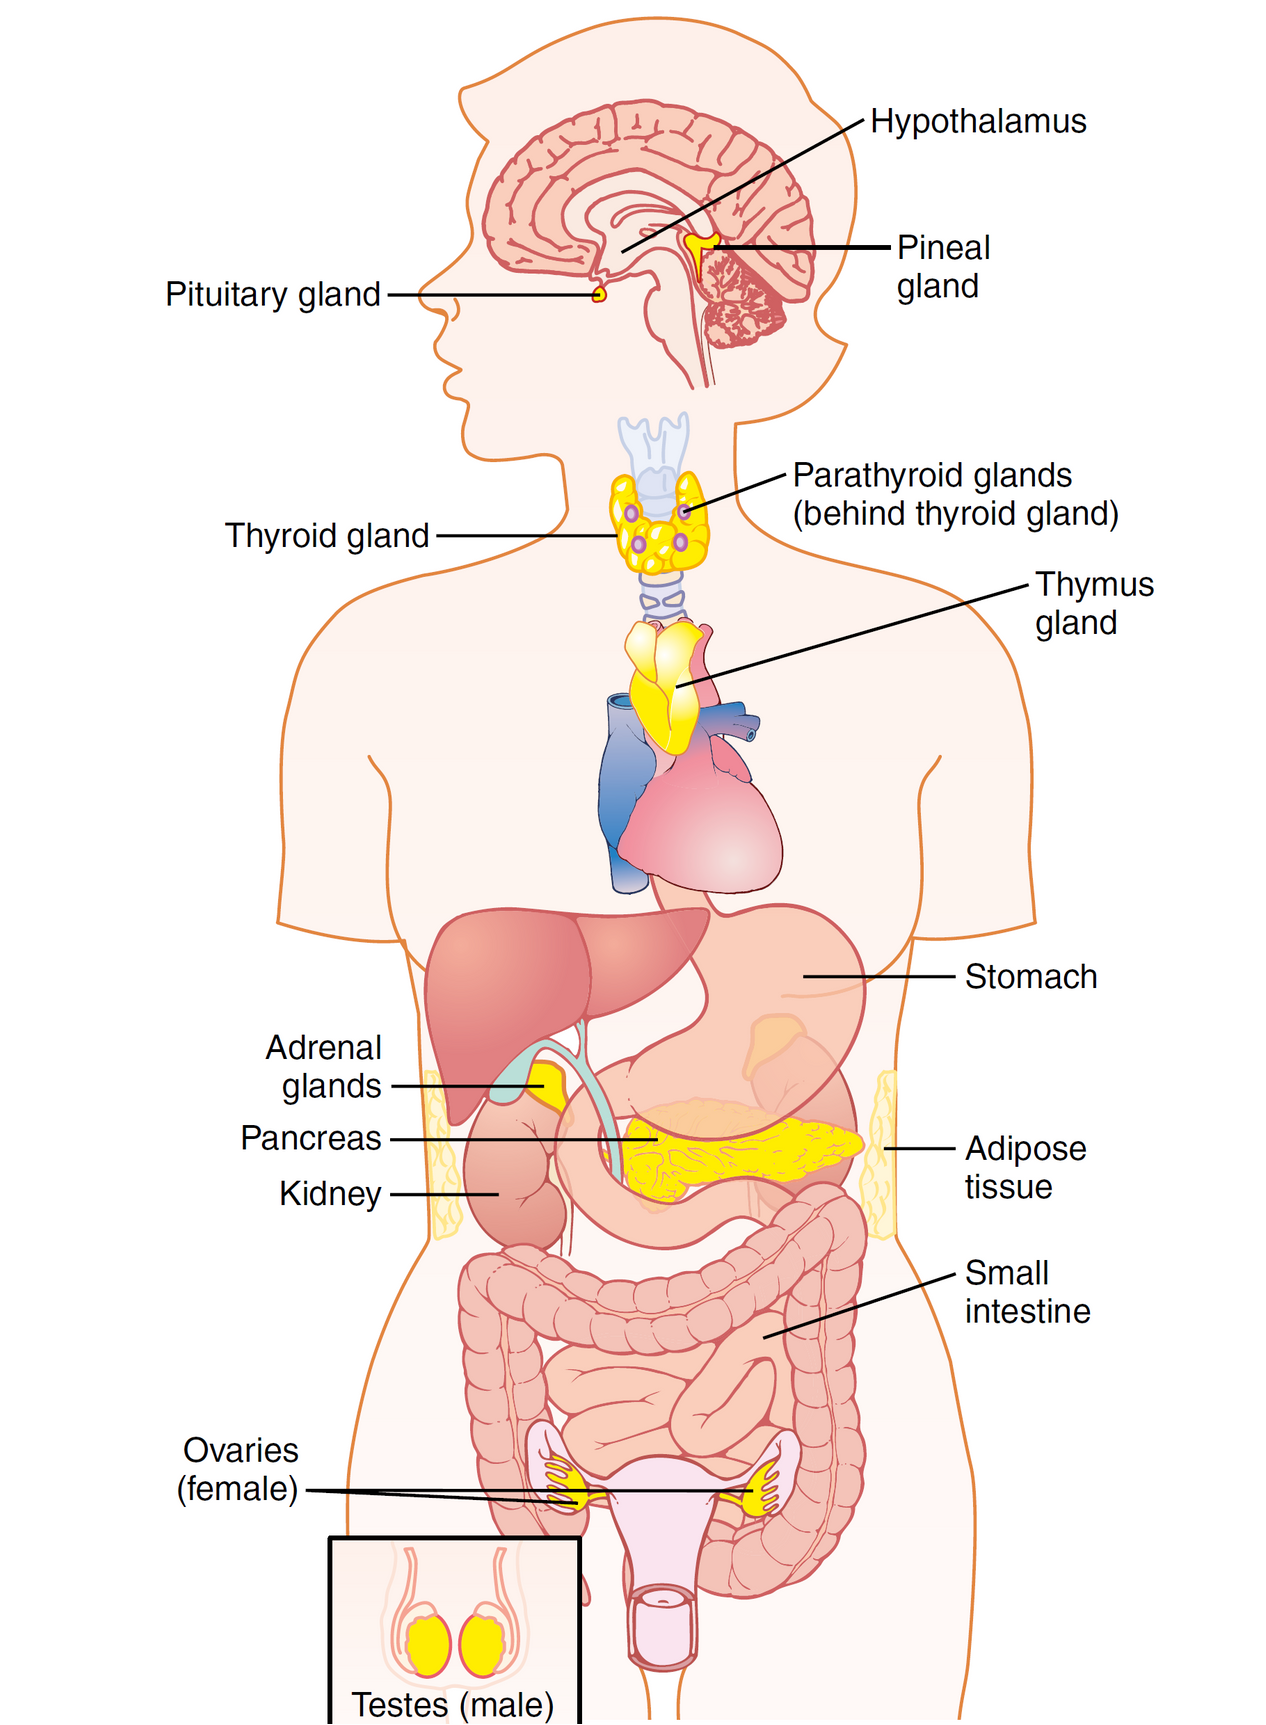

قیمت: 108٬000 تومان - دسته بندی فایل: علوم پزشکیپاورپوینت غدد درون ریز

فروش ویژه پاورپوینت حرفه ای غدد درون ریز با یک تخفیف استثنایی فقط 103134 هزارتومان تعداد اسلاید : 70 اسلاید

قیمت: 68٬000 تومان - دسته بندی فایل: علوم پزشکیپاورپوینت هورمون ها و دستگاه درون ریز

فروش ویژه پاورپوینت حرفه ای هورمون ها و دستگاه درون ریز با تخفیف استثنایی فقط 72400 تومان تعداد اسلاید: 32 اسلاید